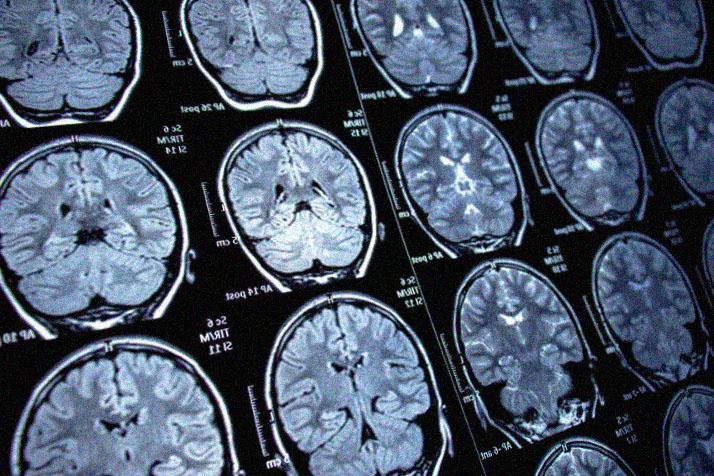

Представьте, что снимок вашего МРТ анализирует нейросеть и за три минуты находит опухоль размером 4 мм — то, что усталый глаз рентгенолога мог пропустить после десятка других снимков. Это не сценарий будущего, такие системы уже работают в российских клиниках. ИИ здесь — не замена врачу, это его «цифровая лупа», улавливающая невидимое. Технология повышает точность диагностики рака до 95%, спасая жизни благодаря раннему выявлению. Но путь в каждую больницу лежит через лабиринт разрешений и вопросов: а можно ли доверять машине? За этим стоит не волшебство, а математика и огромные данные. Нейросети учатся на миллионах помеченных снимков МРТ и КТ — здоровых и с патологиями. После обучения алгоритм умеет: Главное преимущество — скорость и неутомимость. Пока врач изучает один снимок 30-60 минут, ИИ обрабатывает десятки и замечает микрообъекты от 4 мм. Человеческий глаз устает, а вот ИИ — нет Технология вышла за стены лабораторий. Возьмем рак простаты — второй по смертности среди мужчин в Ро

Представьте, что снимок вашего МРТ анализирует нейросеть и за три минуты находит опухоль размером 4 мм — то, что усталый глаз рентгенолога мог пропустить после десятка других снимков. Это не сценарий будущего, такие системы уже работают в российских клиниках. ИИ здесь — не замена врачу, это его «цифровая лупа», улавливающая невидимое. Технология повышает точность диагностики рака до 95%, спасая жизни благодаря раннему выявлению. Но путь в каждую больницу лежит через лабиринт разрешений и вопросов: а можно ли доверять машине?

В Новосибирске нейросети распознают 4 типа опухолей мозга на МРТ, детально выделяя зоны некроза. Это ускоряет планирование операций на дни